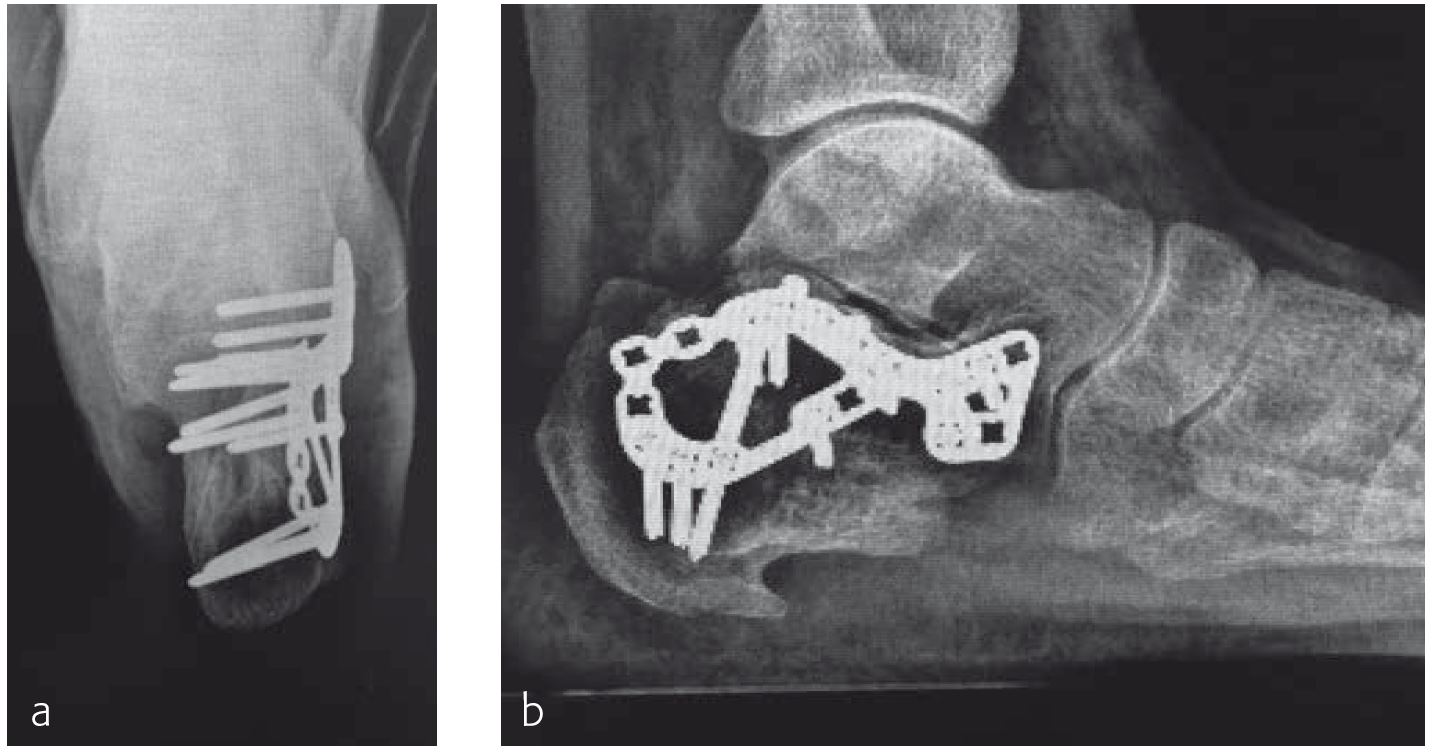

A 70-year-old female patient (Fig 1) had a long history of increasing painful deformity of her foot. She also noted increasing gait problems. There was no history of initial trauma. The examination showed severe rigid flatfoot deformity.

An extended triple arthrodesis was performed. Medially, the new Medial Column Plate was used, securing the talonavicular, naviculocuneiform, and tarsometatarsal joints (Fig 2). The X-plate is lateral and secured the calcaneo-cuboid joint. Two 7.3 mm screws were used to secure the subtalar joint.